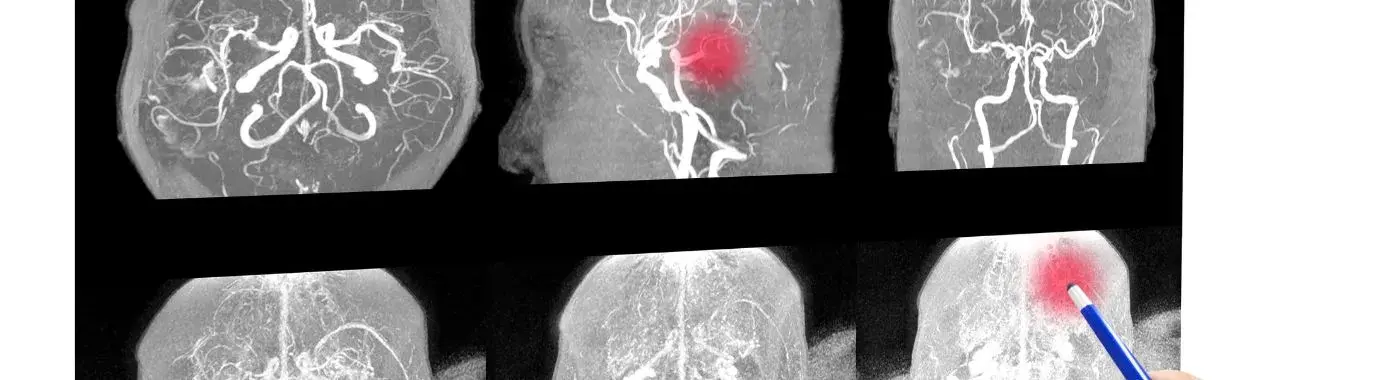

• Imaging Studies: Magnetic resonance imaging (MRI) is the gold standard for diagnosing colpocephaly, as it provides detailed images of the brain's structure.

• Ultrasound: In infants, a cranial ultrasound may be used to assess ventricular size and detect abnormalities.